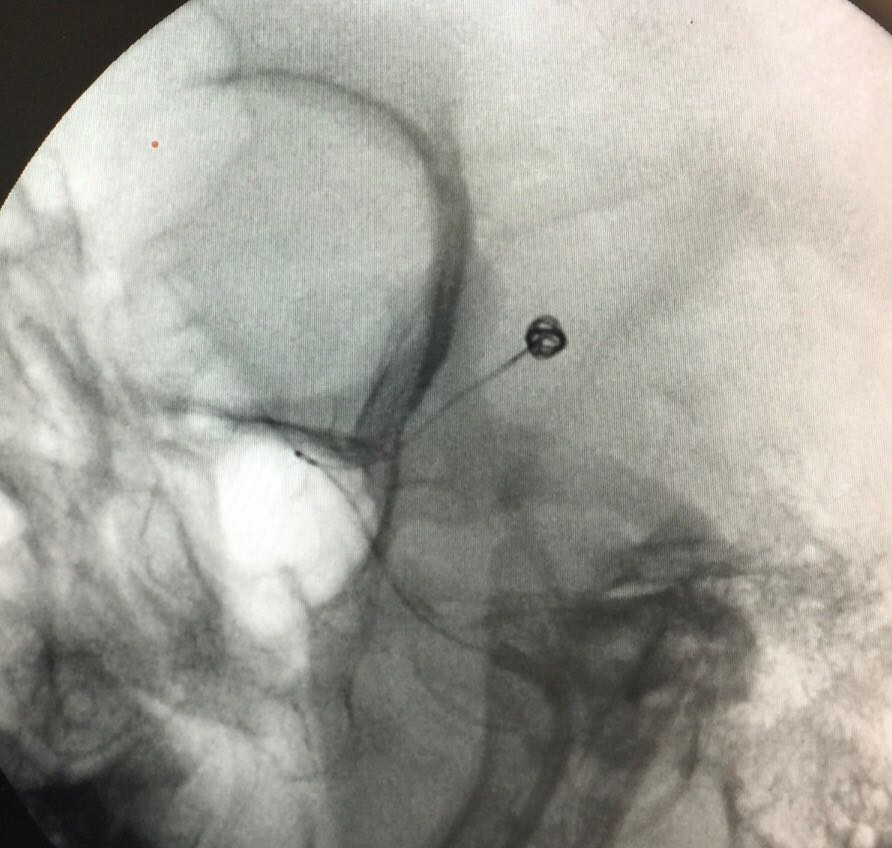

Somos una empresa enfocada en la atención en salud humana por medio del uso imágenes para ver diagnosticos y tratamientos de las diversas patologías con el uso de técnicas mínimamente invasivas en el territorio colombiano en el sector público y privado en búsqueda de una atención oportuna y de calidad a cada uno de nuestros pacientes.